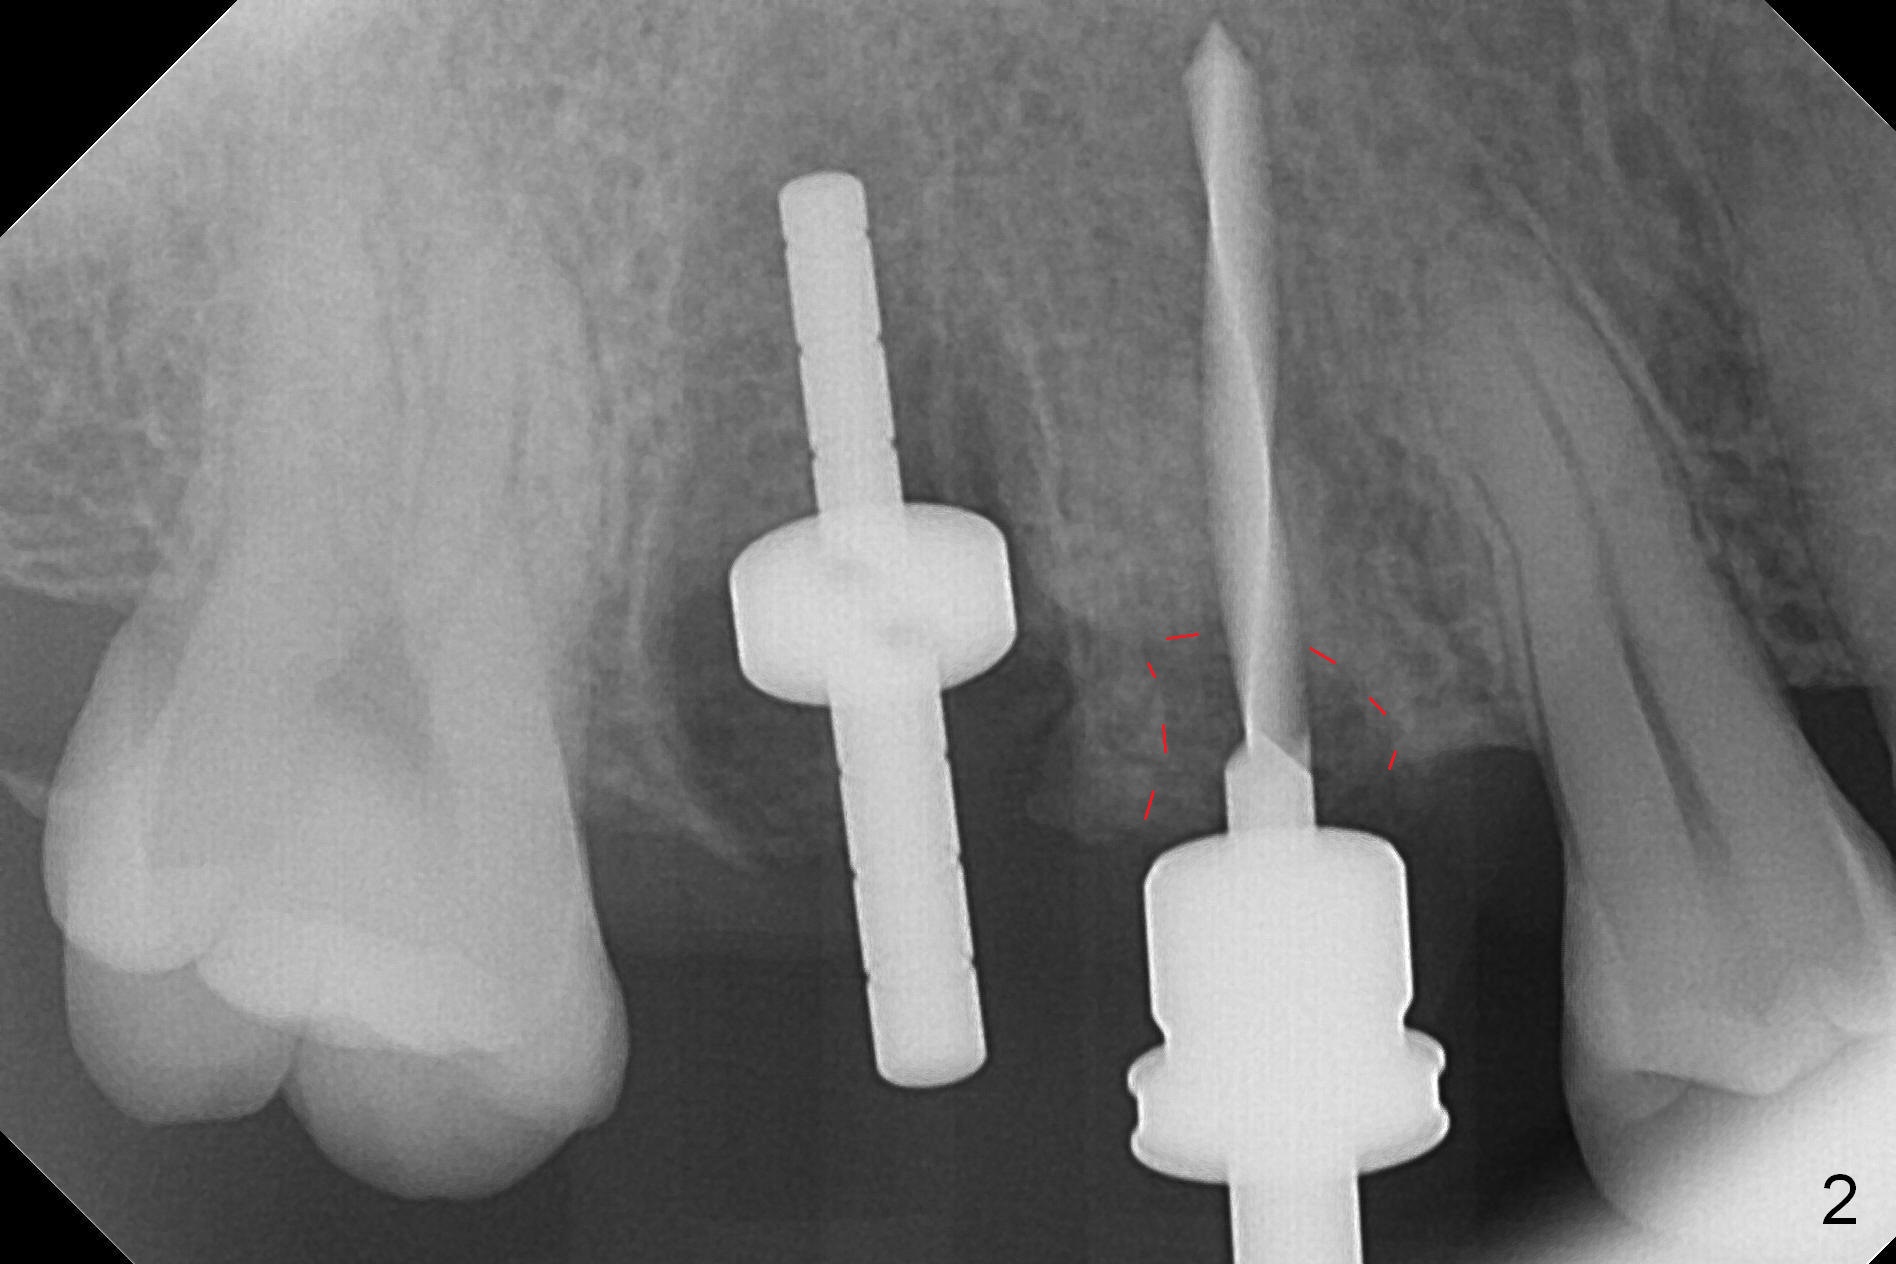

The buccal gingival margin of the residual root at #4 is coronally migrated (Fig.1). The clinical crown height is expected to be short. After wound heals, the abutment mentioned below will be changed to the one with shorter cuff (2 mm for example) with preparation if needed. The margin of the provisional will be fabricated subgingival and bulging so that the gingival margin will be gradually migrated apically.

In contrast, osteotomy at #4 is finished with a single MD 3.3 mm. A 4x13 mm implant is placed with more than 50 Ncm. Pair abutments are immediately placed (6.5x4(3) and 4.5x4(3) mm) for splinted immediate provisional. The remaining socket (Fig.4 red dashed line) is filled with mixture of allograft, autogenous bone and Osteogen (*).